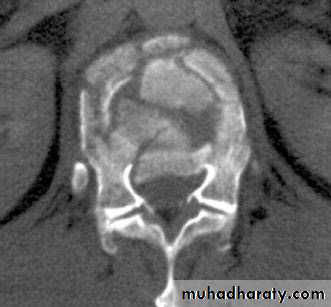

CT: best for bony anatomy.

MRI: best to evaluate soft tissue.

Cauda Equina Syndrome

A surgical emergency.Requires full neurologic examination including rectal examination for anal tone.

Investigations: X-rays initially, but MRI is mandatory as X-rays are usually unremarkable.

Treatment: Emergency decompression-usually discectomy and wide laminectomy within 24 hours.